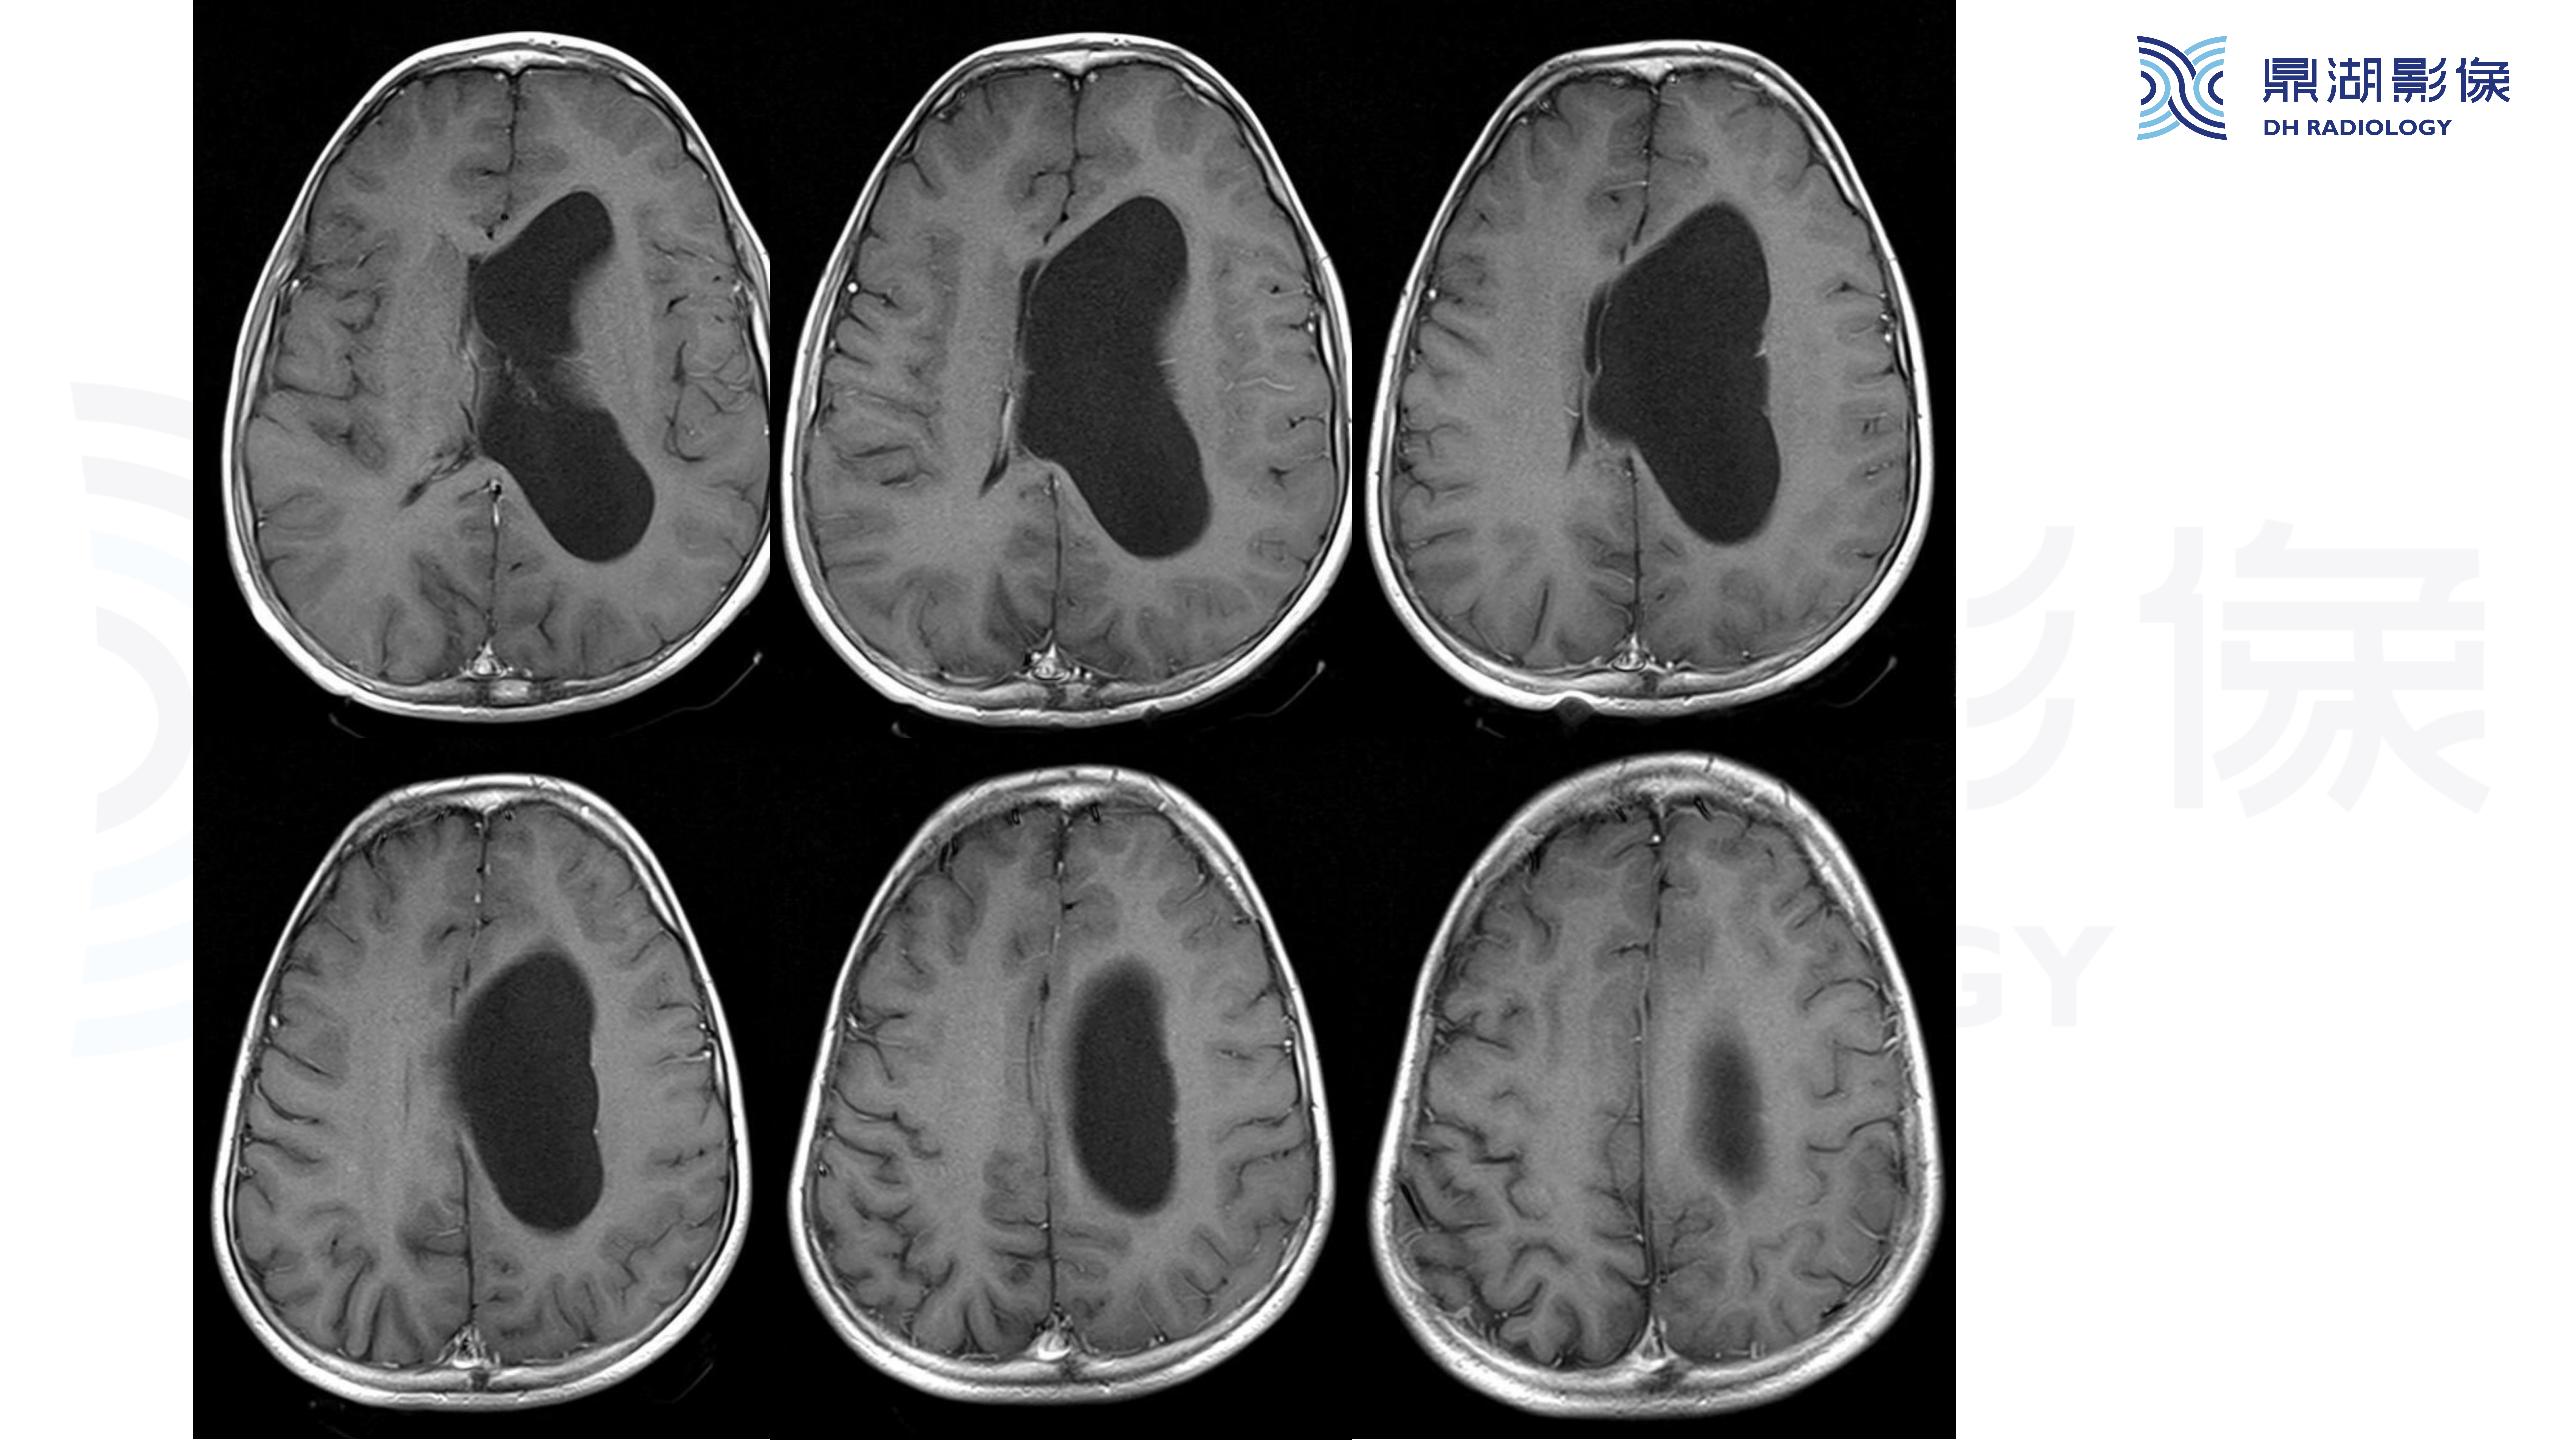

裂隙脑室综合征 (slit ventricle syndrome,SVS)-鼎湖社群读片病例